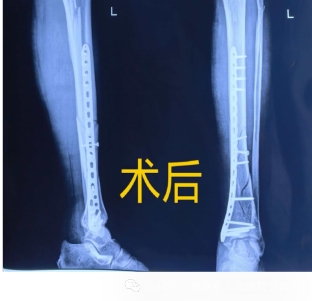

待患肢肿胀消退、皮肤皱褶试验阳性,全身状况达到手术标准后,徐武主治医生根据患者骨折分型、年龄及活动需求,制定闭合复位内固定微创手术方案。该术式无需大范围切开暴露骨折端,依托透视下闭合复位,经皮隧道置入接骨板,具有创伤小、出血少、软组织损伤小,减少了术后切口延迟愈合、不愈合、皮缘坏死风险。固定牢靠、术后恢复快等优势,最大程度保护骨折端血运,降低术后感染与骨折不愈合风险。

术后CT与切口

转入术后病房后,骨科护理团队开启全方位精细化围术期护理。术后严密监测生命体征、防止并发症发生。保持患肢妥善抬高,做好切口清洁换药,严格执行抗感染、抗凝、镇痛、消肿药物治疗。同时强化基础护理与生活照护,耐心安抚患者焦虑情绪,做好健康宣教,讲解术后卧床注意事项、饮食调理要点,促进骨折愈合。患者及家属表示十分满意,对主治医生徐武及全科护理人员送锦旗和感谢信表示满意和认可。